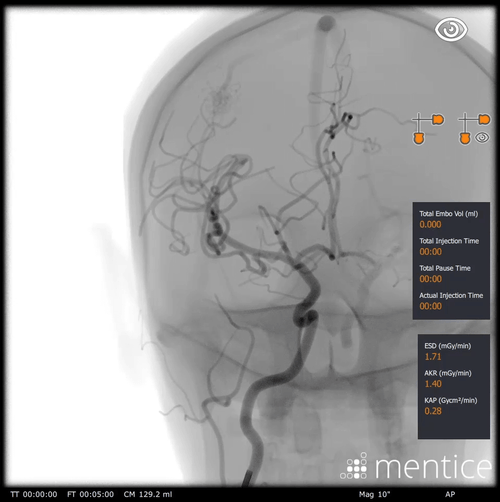

Our anatomical software physics engine, combined with haptic-enabled hardware solutions, creates the optimal environment for procedural adoption, proficiency-based training, patient-specific simulation, and objective skills assessment. Over 350 development years of engineering have created the most advanced IGIT simulation solutions on the market.

Over 2000+ systems delivered worldwide that cover fluoro & echo based learning solutions from head to toe for both Healthcare Professionals and the MedTech Industry.